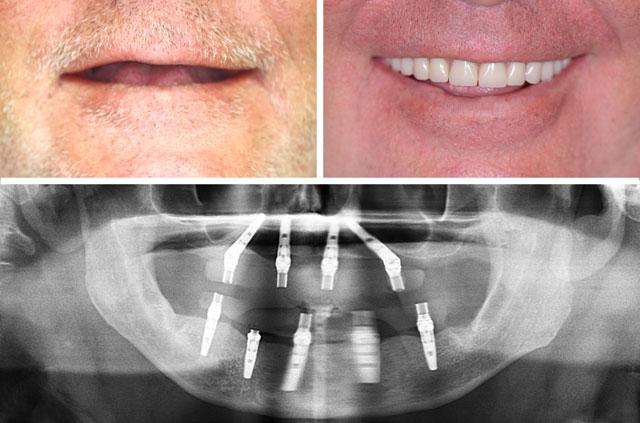

All-on-4 and immediate implant solutions for complete smile restoration. These cases showcase our expertise in full-arch rehabilitation with same-day teeth, providing patients with immediate functional and aesthetic results.

Each case demonstrates the transformative power of dental implants, from single tooth replacement to full-arch restoration. Our All-on-4 Teeth-In-A-Day technique provides immediate results and long-term stability.

What is the All-on-4 Technique?

All-on-4 is a revolutionary dental implant technique that uses just four strategically placed implants to support a full arch of replacement teeth. The posterior implants are angled at 30-45 degrees to maximize bone contact and avoid anatomical structures like the maxillary sinus or inferior alveolar nerve. This innovative approach allows for immediate loading with a temporary prosthesis, providing same-day teeth and eliminating the need for lengthy healing periods between procedures.